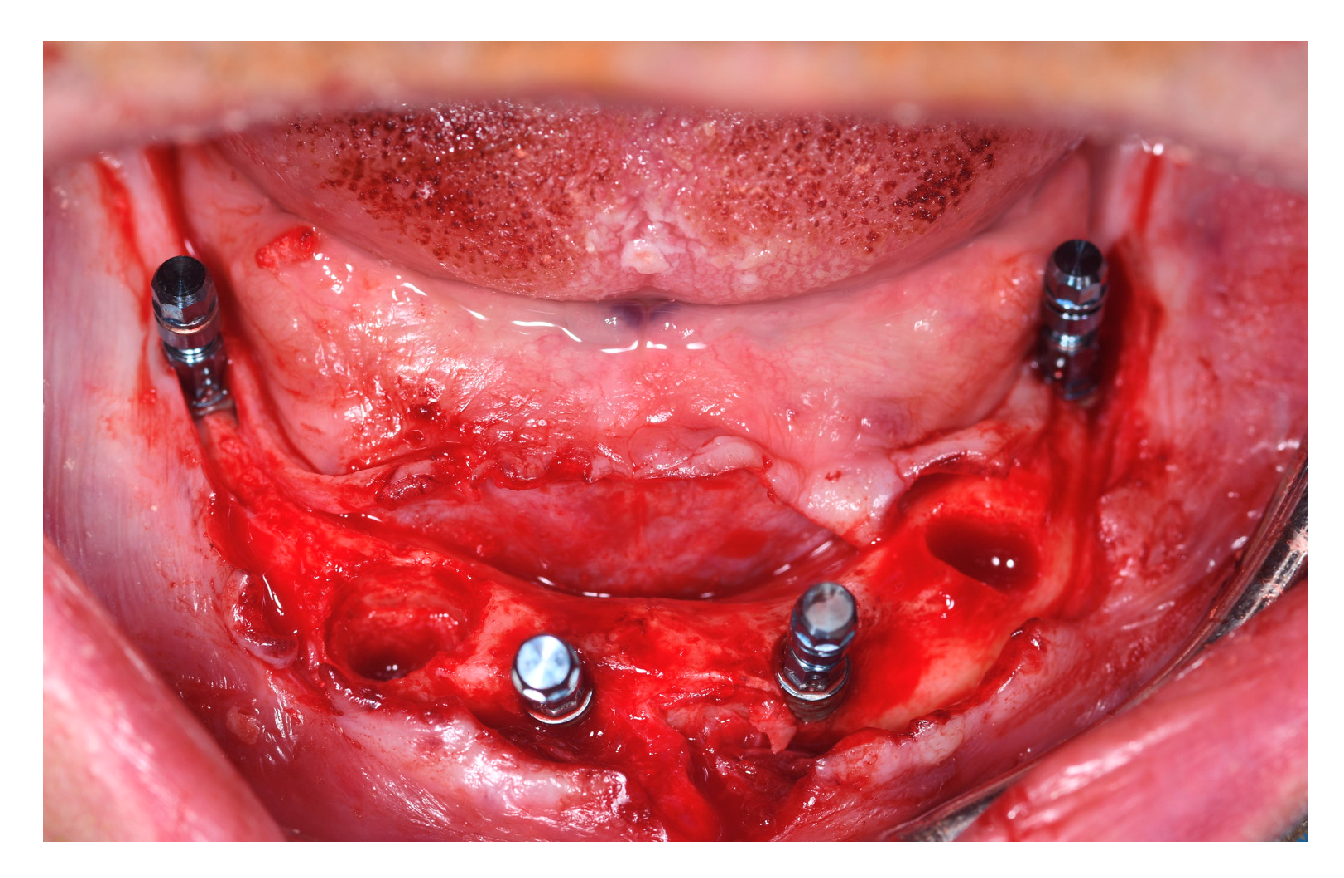

A full thickness flap was raised from molar to molar, and flap elevation was extended on the buccal sides of the maxilla and the mandible, isolating and preserving the anatomical structures. Minimal ostectomy was performed when necessary to compensate for bone discrepancies (Figure 2).

Figure 2. (a) Intraoral pictures of a mandibular case after teeth extraction and flap elevation; (b) a minimal ostectomy was performed in order to compensate for bone discrepancies.